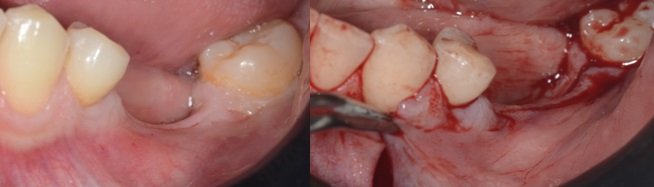

Planejamento da incisão : a incisão poderá ser planejada no modelo de estudo e demarcada com caneta ou lápis cirúrgico na boca facilitando sua visualização (fig. 3 e 4). A incisão deve ser maior que a área a ser operada indo da parte distal posterior até o último dente remanescente do lado a ser operado, devendo ser na crista óssea terminando em sulcular até os dois últimos dentes ou poderá ir em direção ao lábio aumentando assim a visualização do campo a ser operado.

Anestesia : deve ser somente infiltrativa no inicio da cirurgia, fazemos o descolamento do tecido, exposição do forâmen mentoniano, colocação do guia cirúrgico e marcamos com a fresa piloto ou lança a posição dos implantes a serem instalados.